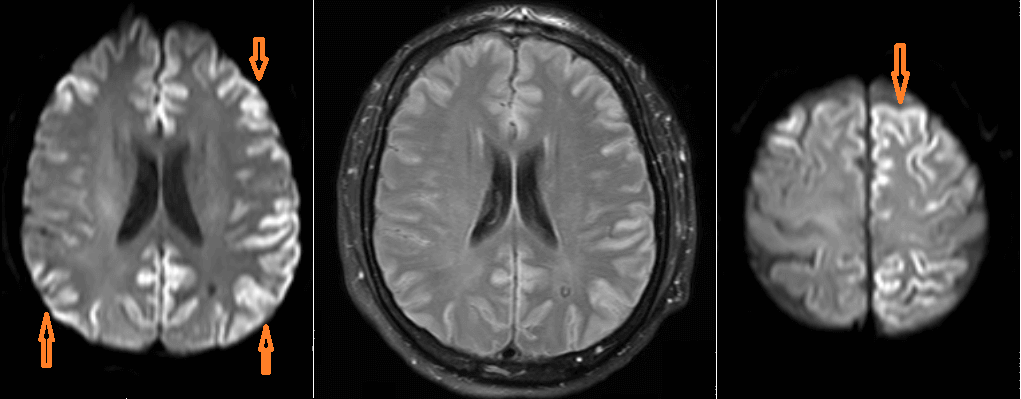

Imaging: Cortical ribboning in DWI sequences is the most common finding on neuroimaging; but this finding is nonspecific and imaging is often more helpful in ruling out other neuropathology.

Classic CJD displays the most prominent spongiform changes in the regions most commonly seen affected on DWI imaging, including cerebral cortex, cerebellar molecular layer, the putamen and caudate, and the thalamus. The Heidenhain variant shows these changes prominently in the occipital cortex.